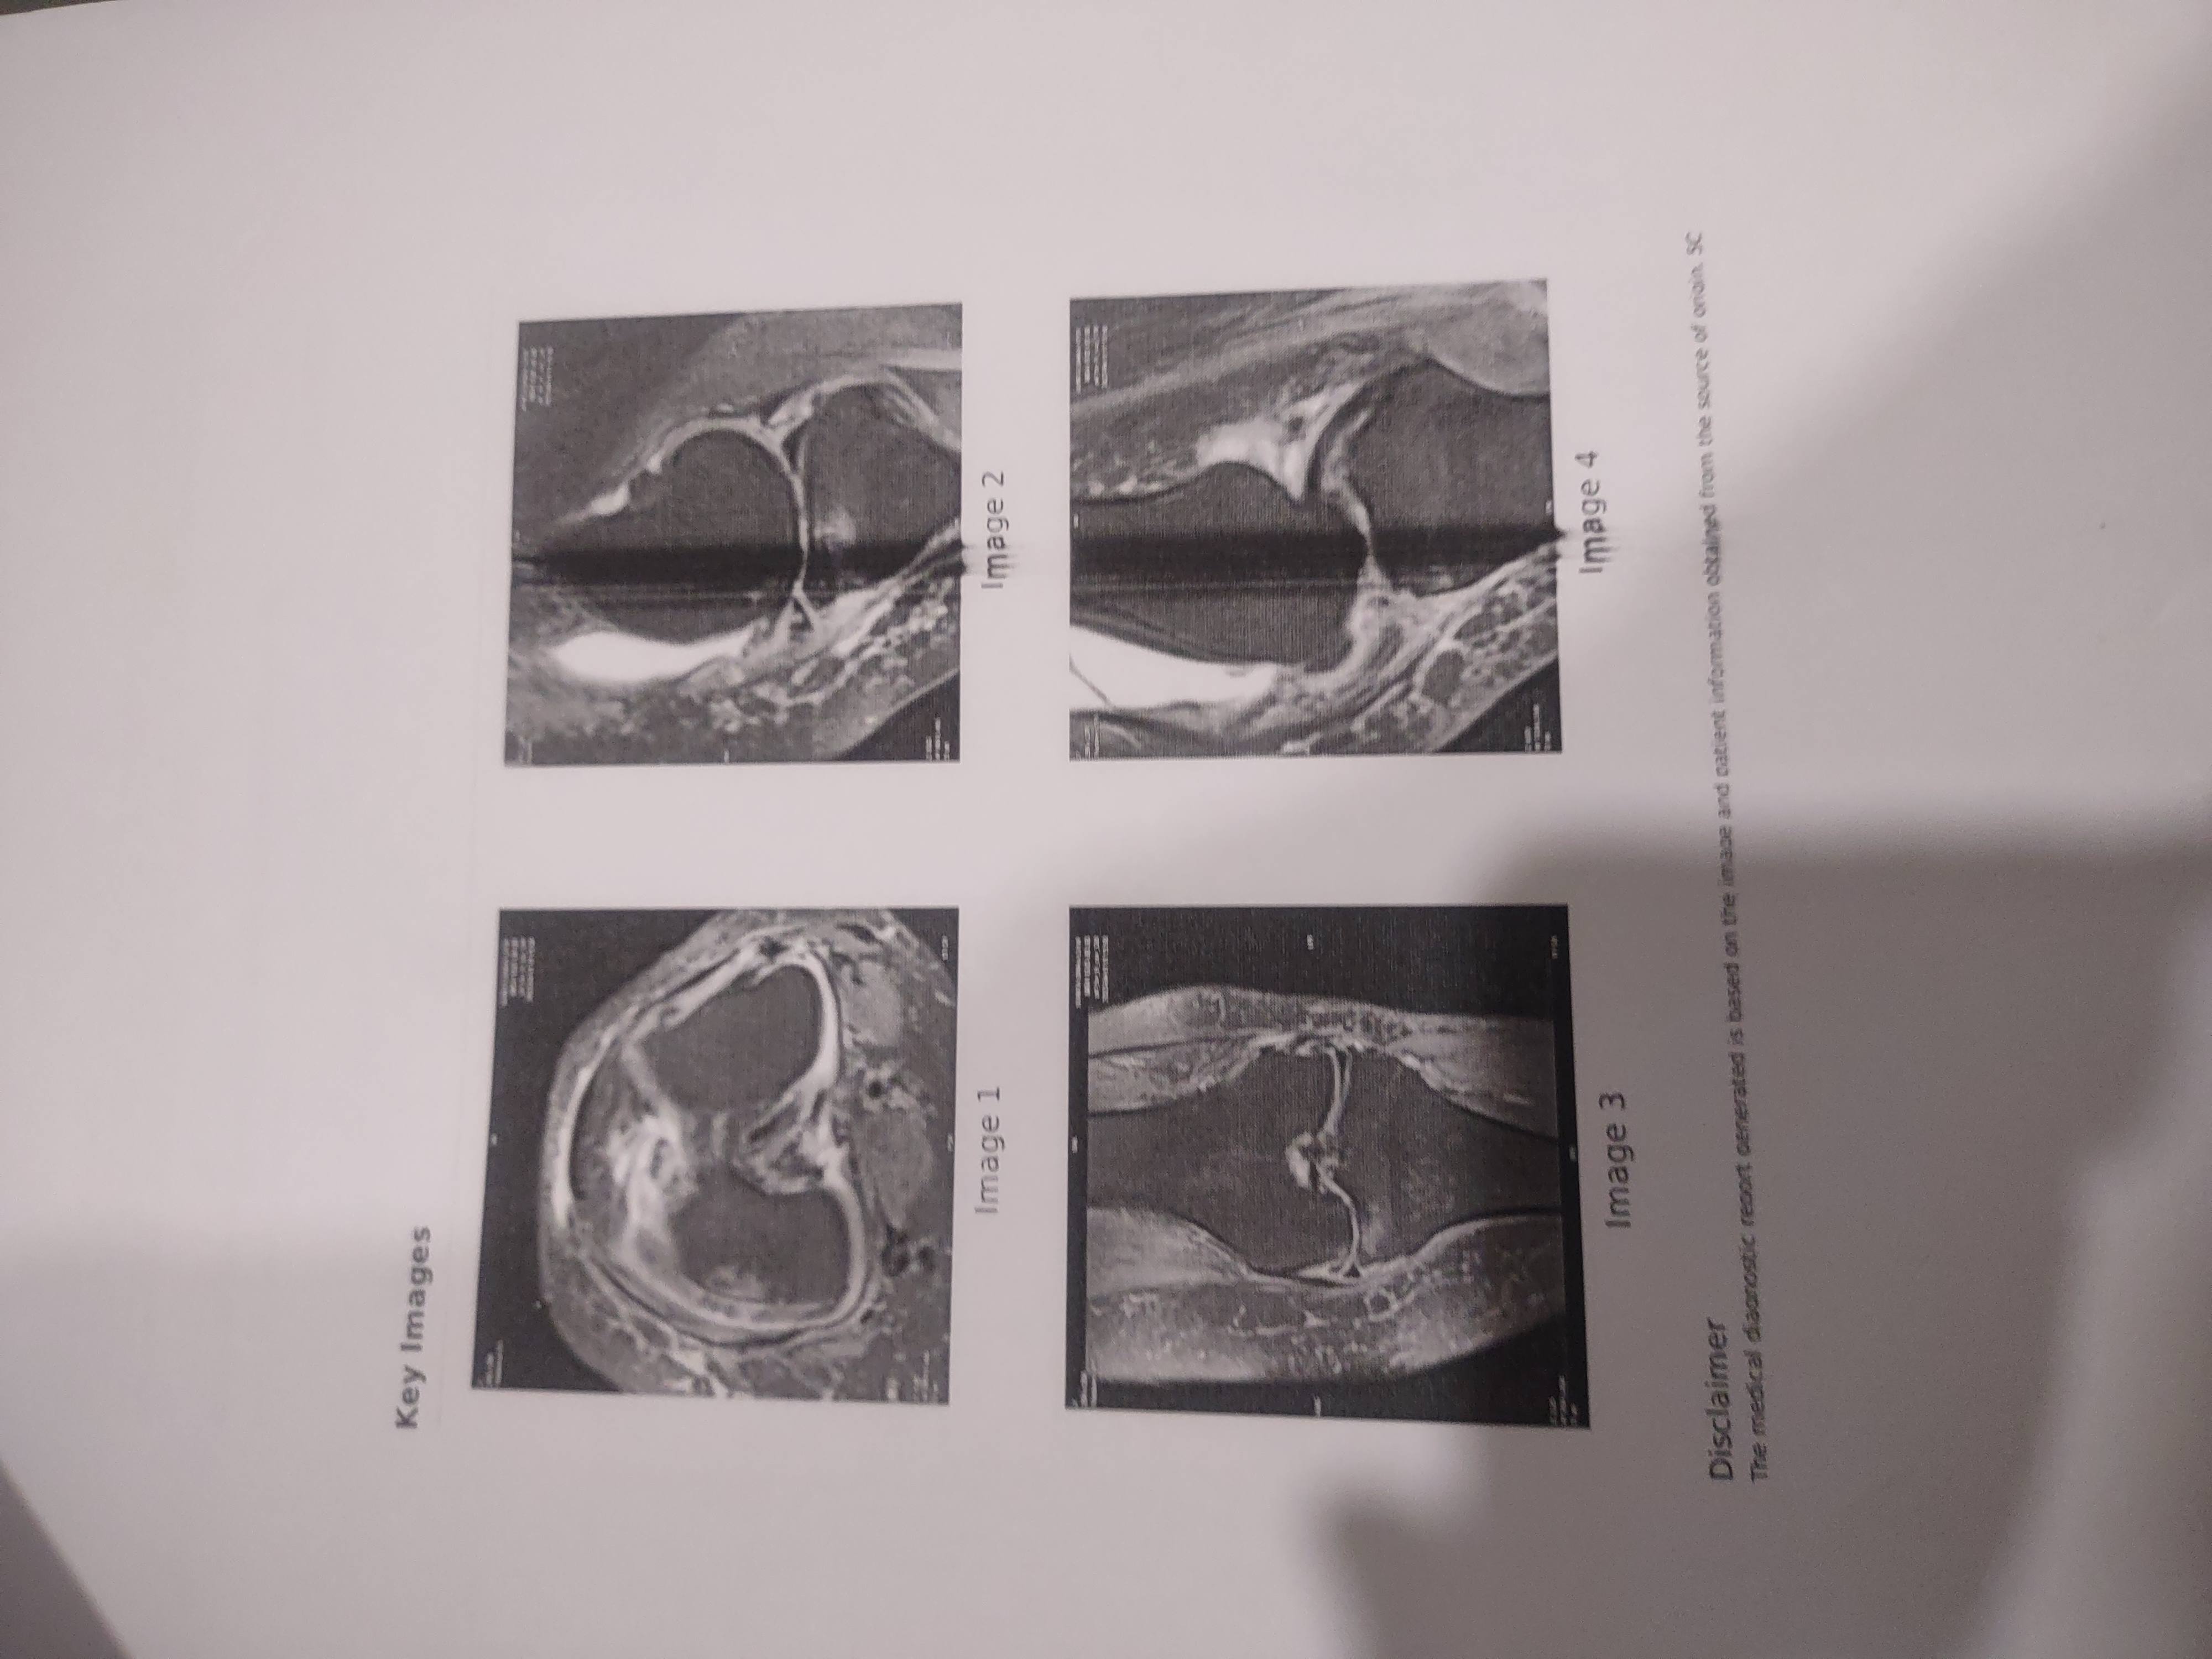

Once synovial fluid is removed and after removal it is found that ACL is damaged then patients does not have any option except to go for knees replacement so what is remedy before going for synovial fluid removal